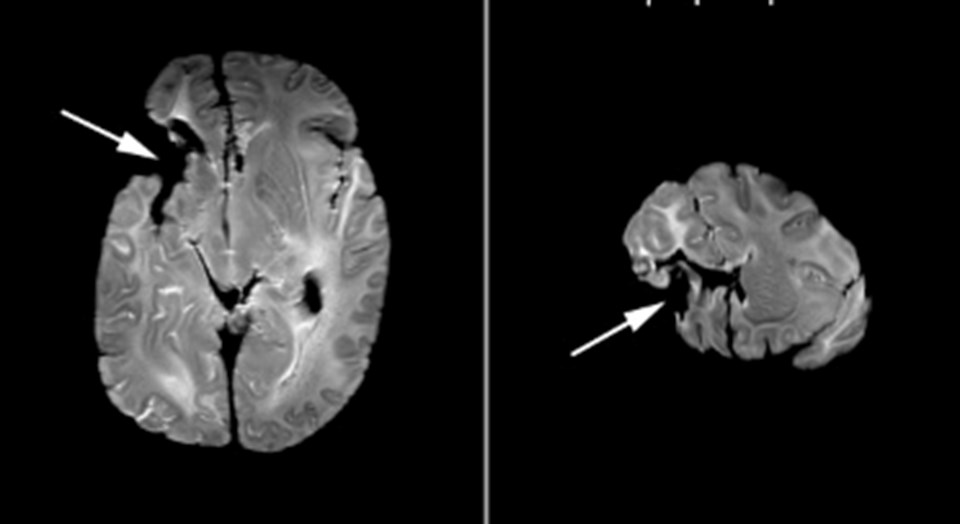

Leborne'un 2007 yılında çekilen beynine ait MRI.

Leborne'un 2007 yılında çekilen beynine ait MRI.